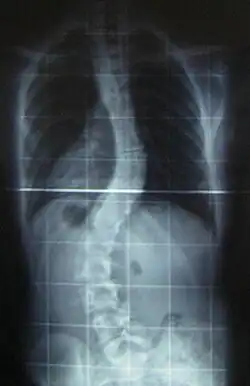

When scoliosis is suspected, weight-bearing, full-spine AP/coronal (front-back view) and lateral/sagittal (side view) X-rays are usually taken to assess the scoliosis curves and the kyphosis and lordosis, as these can also be affected in individuals with scoliosis. Full-length standing spine X-rays are the standard method for evaluating the severity and progression of scoliosis, and whether it is congenital or idiopathic in nature. In growing individuals, serial radiographs are obtained at 3- to 12-month intervals to follow curve progression, and, in some instances, MRI investigation is warranted to look at the spinal cord.[80] An average scoliosis patient has been in contact with around 50–300 mGy of radiation due to these radiographs during this period.[81]

The standard method for assessing the curvature quantitatively is measuring the Cobb angle, which is the angle between two lines, drawn perpendicular to the upper endplate of the uppermost vertebra involved and the lower endplate of the lowest vertebra involved. For people with two curves, Cobb angles are followed for both curves. In some people, lateral-bending X-rays are obtained to assess the flexibility of the curves or the primary and compensatory curves.